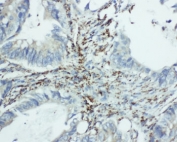

IHC-P: EIF6 antibody testing of human intestine cancer tissue (1)